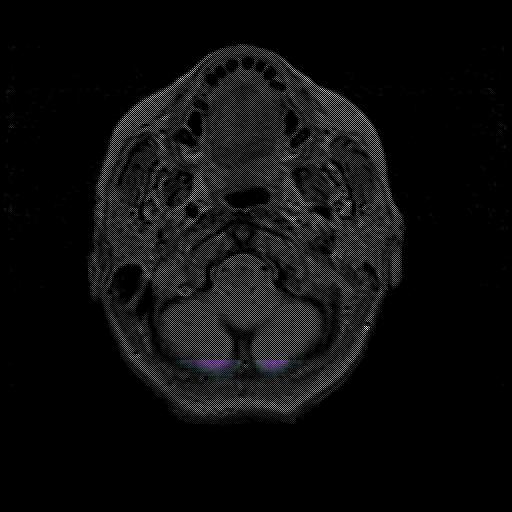

overlay : Slice 5

Slice 5

MRCBFCBF with

T1PDT2T1PDT2